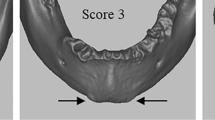

An example of the differences/similarities observed when comparing the dry bone- and virtual 3D models is demonstrated in Fig. 2, exemplifying a trait that scored well (pubic angle), and Fig. 3, illustrating the differences observed in a feature that performed poorly (pre-auricular sulcus).

A male and female example of a trait that performed poorly is the pre-auricular sulcus, on dry bone (a) and on virtual 3D models; the in-house research software package (b) and MeshLab (c). The arrows indicate the region of interest with the sulcus being present (*) on the female pelvis. Note that the pre-auricular sulcus is clearly visible on the dry bone, but invisible when viewed with the in-house software and poorly defined when looking at the reconstruction with MeshLab